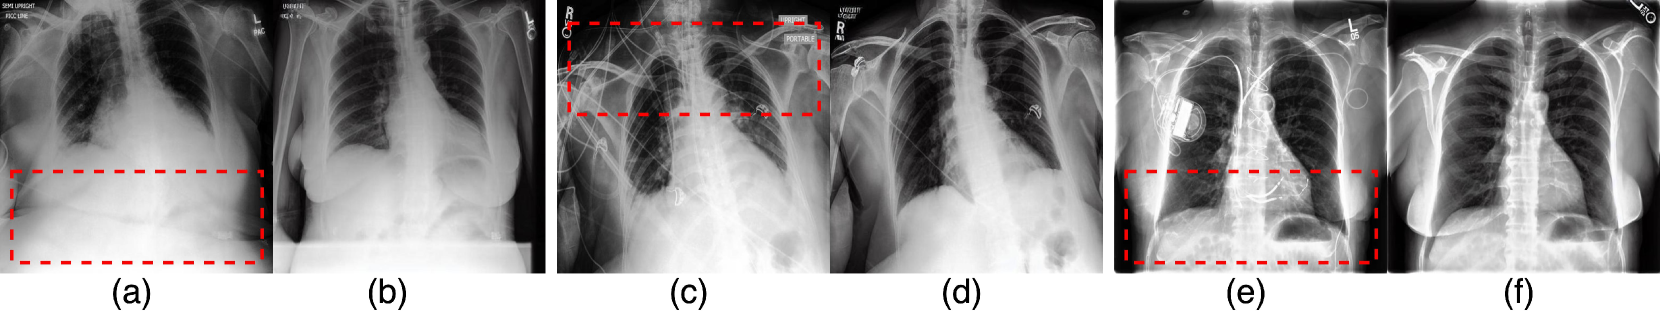

Qualitative Evaluations Our qualitative evaluation demonstrates two primary capabilities of our method: (i) the ability to remove and, for completeness, add medical devices to the original image, and (ii) the ability to emulate distinct visual pathologies of different diseases.

Chest radiographs contain a variety of medical devices [Gambato et al.(2023)Gambato, Scotti, Borsari, Zambon Bertoja, Gabrieli, De Cassai, Cester, Navalesi, Quaia, and Causin] such as chest tubes for draining air, blood, or fluid from the pleural space, surgical clips that are often visible after procedures like axillary node dissection, or pacemakers that regulate heart rhythm, typically seen as a small box near the clavicle [Mathew et al.(2019)Mathew, Alexander, Patel, and Low]. These devices vary in shape, size and position in the X-ray image. Our method, PRISM, can remove medical devices, demonstrating robust performance across various device types and positions without any external classifier-based supervision or image-level mask/annotations.

Refer to caption

Figure 3: Sample pairs of original and CF images demonstrate the capability of PRISM to remove and add medical devices (e.g. wires, pacemaker) in high resolution. Left: CF images with medical devices removed. Language guidance is T𝑇Titalic_T: chest xray of the patient with lots of medical devices, Tsuperscript𝑇T^{\prime}italic_T start_POSTSUPERSCRIPT ′ end_POSTSUPERSCRIPT: chest xray of the patient without medical devices. Note that the baseline method cannot properly remove medical devices; Right: CF images with added medical devices. Language guidance is T𝑇Titalic_T: chest xray of the patient with no support devices, Tsuperscript𝑇T^{\prime}italic_T start_POSTSUPERSCRIPT ′ end_POSTSUPERSCRIPT: chest xray of the patient with lots of support devices.

In Fig. 3, we show how, by using language guidance, we can remove complex medical devices from the given image without altering the pathology of the disease. We also compare our framework to a baseline method, GANterfactual [Mertes et al.(2022)Mertes, Huber, Weitz, Heimerl, and André], a classifier-guided CF generator. This method relies on the gradient from a pre-trained classifier for guidance and fails to remove devices from the image. Next, we evaluate our method’s ability to effectively differentiate between diseases during CF image generation. Specifically, Fig. 4 demonstrates PRISM’s performance in generating CFs for two diseases: Pleural Effusion and Cardiomegaly.